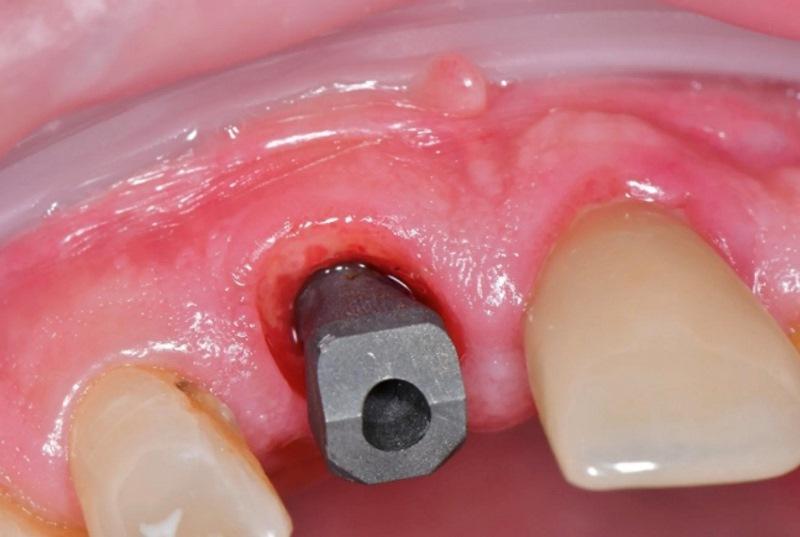

Хирургический шаблон введен в полость рта для проверки посадки относительно соседних зубов и стабильности на дуге. Остеотомия выполнена с применением направляемого хирургического набора (Ritter Guided Kit, Ritter Implants) через шаблон для немедленной установки имплантата в область зуба 1.1. Стартовая остеотомия выполнена пилотным сверлом 2,8 мм из направляемого набора (Ritter Implants), введенным через шаблон для обеспечения точной ориентации и позиционирования. Далее проведена оссеоденсификация борами Densah (Versah), в частности 3,0 и 3,5 мм, в обратном режиме (против часовой стрелки) согласно протоколу производителя, при 1 200 об/мин с обильной ирригацией физиологическим раствором. Имплантат (Spiral SB/LA Implant, 4,2×13 мм, Ritter Implants) установлен через хирургический шаблон в полости рта с позиционированием на 3 мм ниже уровня гребня. Вкручивание достигнуто при моменте 25 Н·см. Индивидуальный формирователь десны подготовлен и отложен до этапа установки.

Аллотрансплантат MinerOss (BioHorizons) смешан с PRF, полученным в начале приема, для изготовления смеси «липкая кость». Смесь введена для заполнения гребневых щелей между стенками лунки и имплантатом. Затем на имплантат установлен индивидуальный формирователь десны.

Выполнена прицельная рентгенограмма для проверки посадки формирователя десны и документирования позиции имплантата относительно анатомических структур (Фото 6). Для содействия формированию сгустка между мягкими тканями и «липкой костью» на десну наложено давление. Наложены швы 4-0 из кетгута для удержания мягких тканей в контакте с индивидуальным формирователем десны. В полости рта установлен временный ретейнер Essix; пациенту предписано носить его круглосуточно, снимая только для проведения гигиены, до следующего приема через 2 недели (Фото 7).